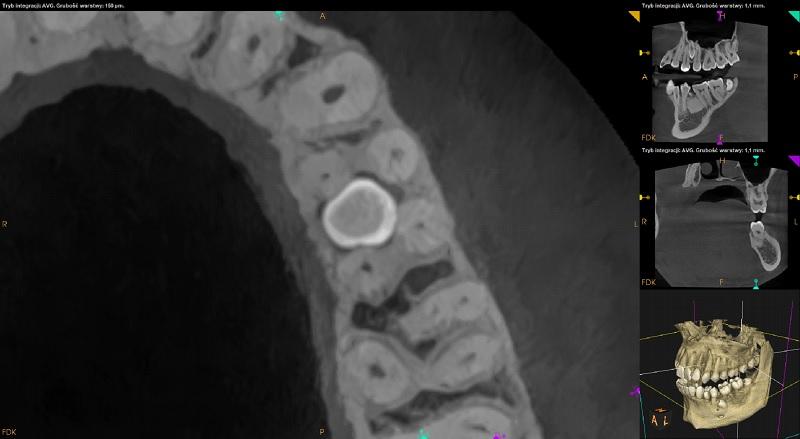

Żuchwa

Pomiędzy korzeniami zębów 36 i 35 widoczne dwa zatrzymane zęby dodatkowe. Ząb po stronie przedsionkowej położony pionowo skośnie, koroną skierowany w stronę mezialną i policzkową. Wierzchołek korzenia w kontakcie z kanałem nerwu zębodołowego dolnego.

Ząb po stronie językowej położony skośnie, koroną skierowany w stronę mezialną. Resorpcja korzeni zębów sąsiednich niewidoczna. Pomiędzy zębami dodatkowymi ognisko zagęszczenia struktury kostnej.

Po stronie przedsionkowej zęba 34 ząb dodatkowy. Ząb 34 zrotowany w stronę dystalną. Wierzchołek korzenia dodatkowego zagięty.

Pomiędzy korzeniami zębów 34 i 33 widoczny zatrzymany mikrodontyczny ząb nadliczbowy.